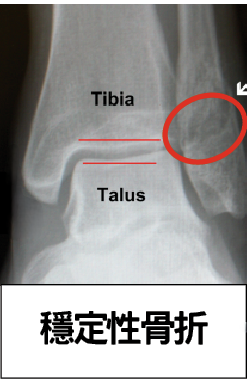

A15a - 可調限位高身步行靴 (45cm)

主適用症狀:

• - 阿基里斯跟腱重建或縫補術後使用

• - 下脛骨骨折

副適用症狀:

• - 穩定性足踝骨折, 早期拆除石膏後使用

A17 - 高身步行靴 (45cm)

適用症狀

• - 有瘀血及腫脹

• - 二、三、四級足踝扭傷(嚴重拗柴)

• - 足踝脫臼

• - 穩定性足踝骨折

• - 足踝手術後康復期使用